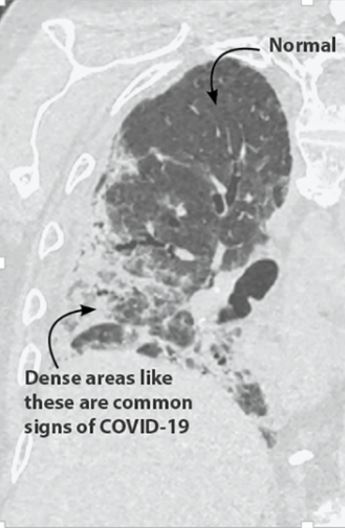

Ултразвук

Ултразвучни апарати користе звучне таласе високе фреквенције уместо зрачења. Сонда повезана са ултразвучним апаратом шаље и прима милионе звучних таласа кроз циљани део тела сваког секунда, што би у случају COVID-19 пацијената била плућа. Када ови таласи наиђу на препреку, као што је она између меког ткива и течности или меког ткива и костију, они се враћају у сонду и приказују на екрану.

Ултразвучни апарати нису скупи и доступнији су него рентген апарати и СТ скенери. С обзиром да су мали, мобилни и лаки за деконтаминацију, лако се могу користити поред кревета пацијента, у амбулантама или тријажним деловима. Пошто не користе зрачење, могу се чешће примењивати без додатног ризика за пацијенте и здравствене раднике.

Ултразвучне слие се истог тренутка приказују на екрану тако да обучени здравствени радник може на лицу места да процени стање пацијента. Ултразвучни снимци плућа су добра полазна тачка код дијагностификовања пацијената са респираторним проблемима који могу да указују на COVID-19 инфекцију. Међутим, пошто ултразвук плућа приказује само периферне делове и зависе од онога ко га користи, СТ скен и рентгенски снимак су неопходни како би се поставила поузданија дијагноза на COVID-19 и омогућило даље праћење развоја болести код пацијента.